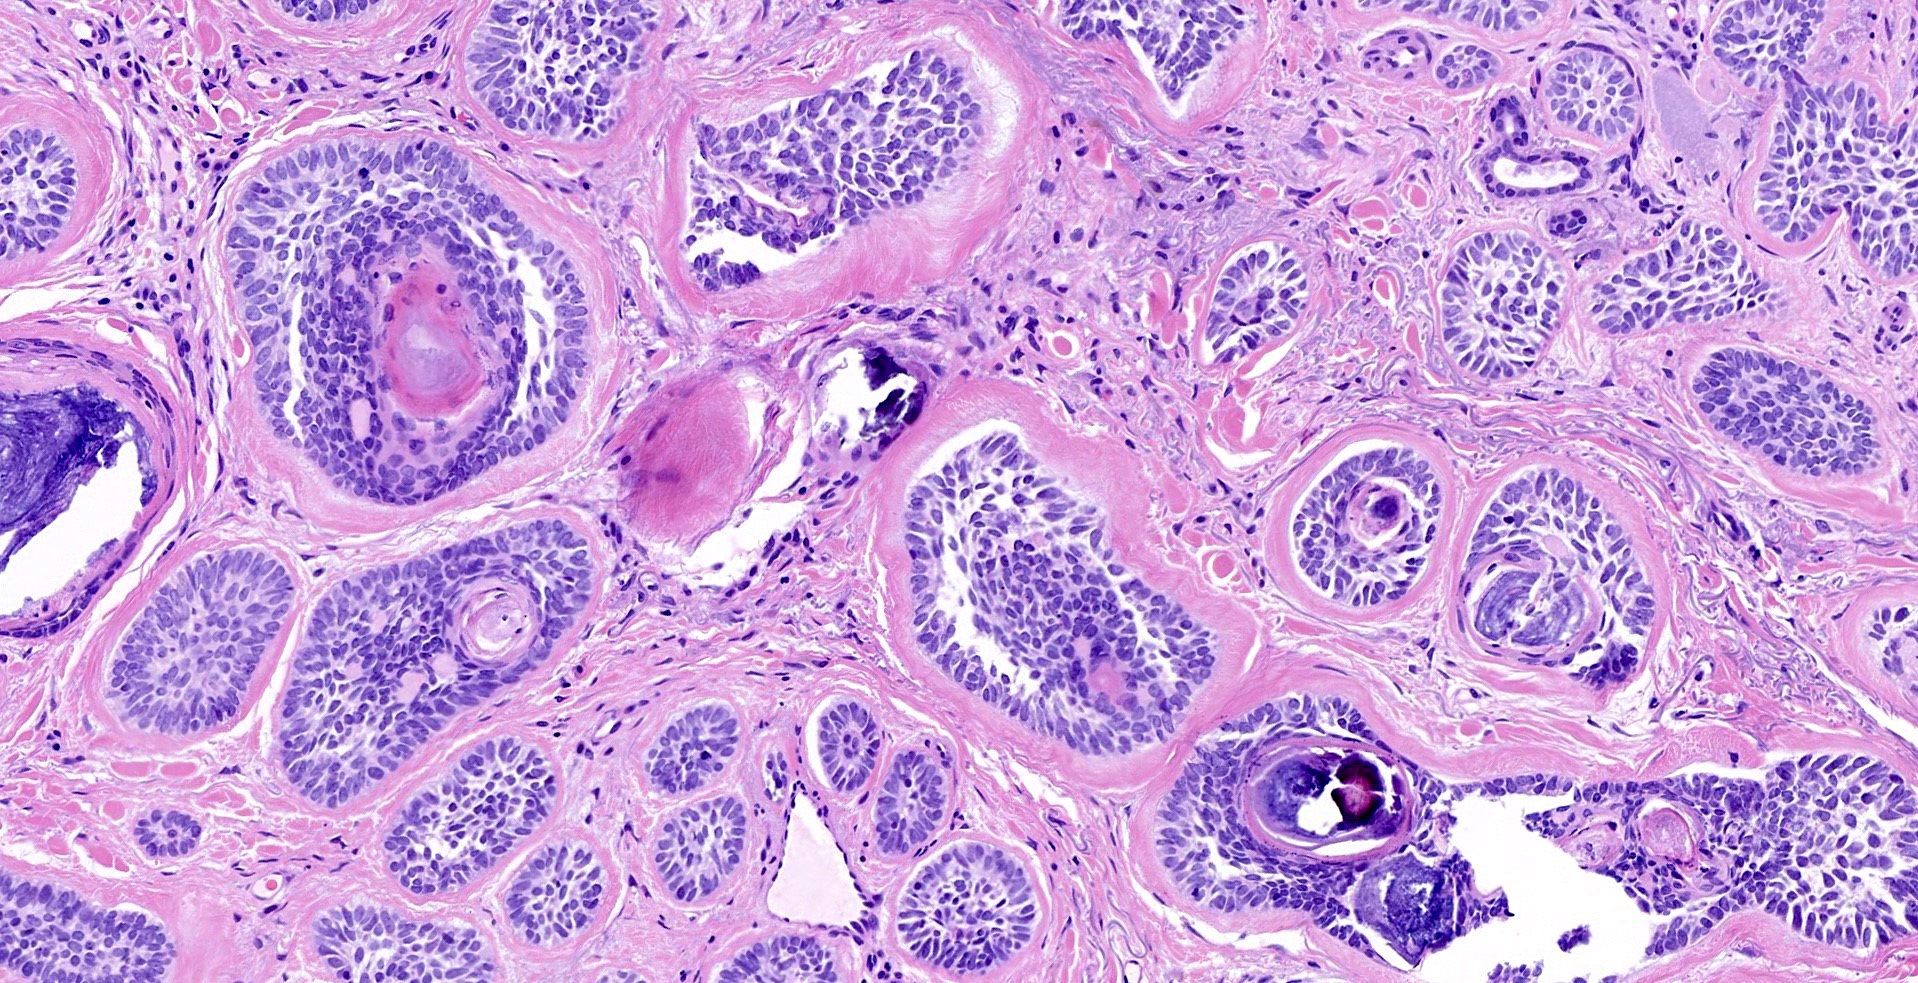

Common variants (Calonje: McKee's Pathology of the Skin, 5th Edition, 2019)

- Nodular and nodulocystic BCC

- Relatively circumscribed mass

- Epidermal or follicular attachment variably present

- Large basaloid lobules with peripheral nuclear palisade

- Lobules may be solid or show central cyst formation due to excessive mucin production

- Fibromyxoid stroma

- Cleft formation between tumor lobules and stroma

- Pleomorphism is generally mild

- Variable mitotic activity and apoptosis

- Sometimes necrosis en masse

- Keratotic BCC

- Horn cyst formation

Microscopic (histologic) images

Contributed by Antonina Kalmykova, M.D., Phillip H. McKee, M.D., Sate Hamza, M.D., Eduardo Calonje, M.D.,

Wayne Grayson, M.B.Ch.B., Ph.D., James Sampson, M.B.B.S., M.Sc. and Assia Bassarova, M.D., Ph.D.